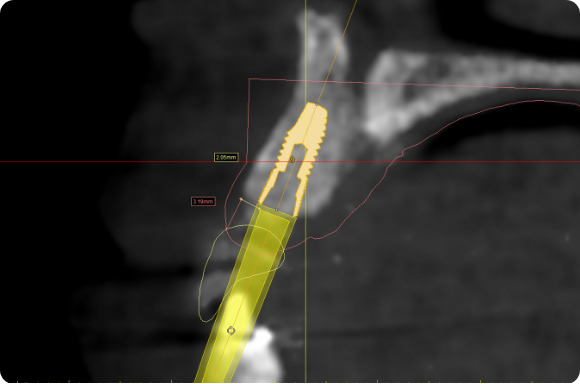

En utilisant un enseignement basé sur les procédures1, ce niveau aidera le clinicien à évoluer vers des concepts chirurgicaux et prothétiques plus avancés grâce au traitement de cas d’implants antérieurs à dent unique.

Tout au long de ce niveau, les cas couvrent des sujets tels que : Évaluation de l’os buccal et apical pour une implantation immédiate, Greffe autour d’implants immédiats (technique de la double zone), Définir l’orientation de l’implant – Les règles de six, Évaluer la stabilité primaire pour une mise en charge immédiate, Options et conceptions de piliers CAO/FAO. À la fin de ce niveau, les participants comprendront comment placer et restaurer un implant à dent unique dans la zone antérieure. Les participants sont invités à poursuivre leur formation au niveau 4, qui se concentrera sur les cas d’implants multiples.